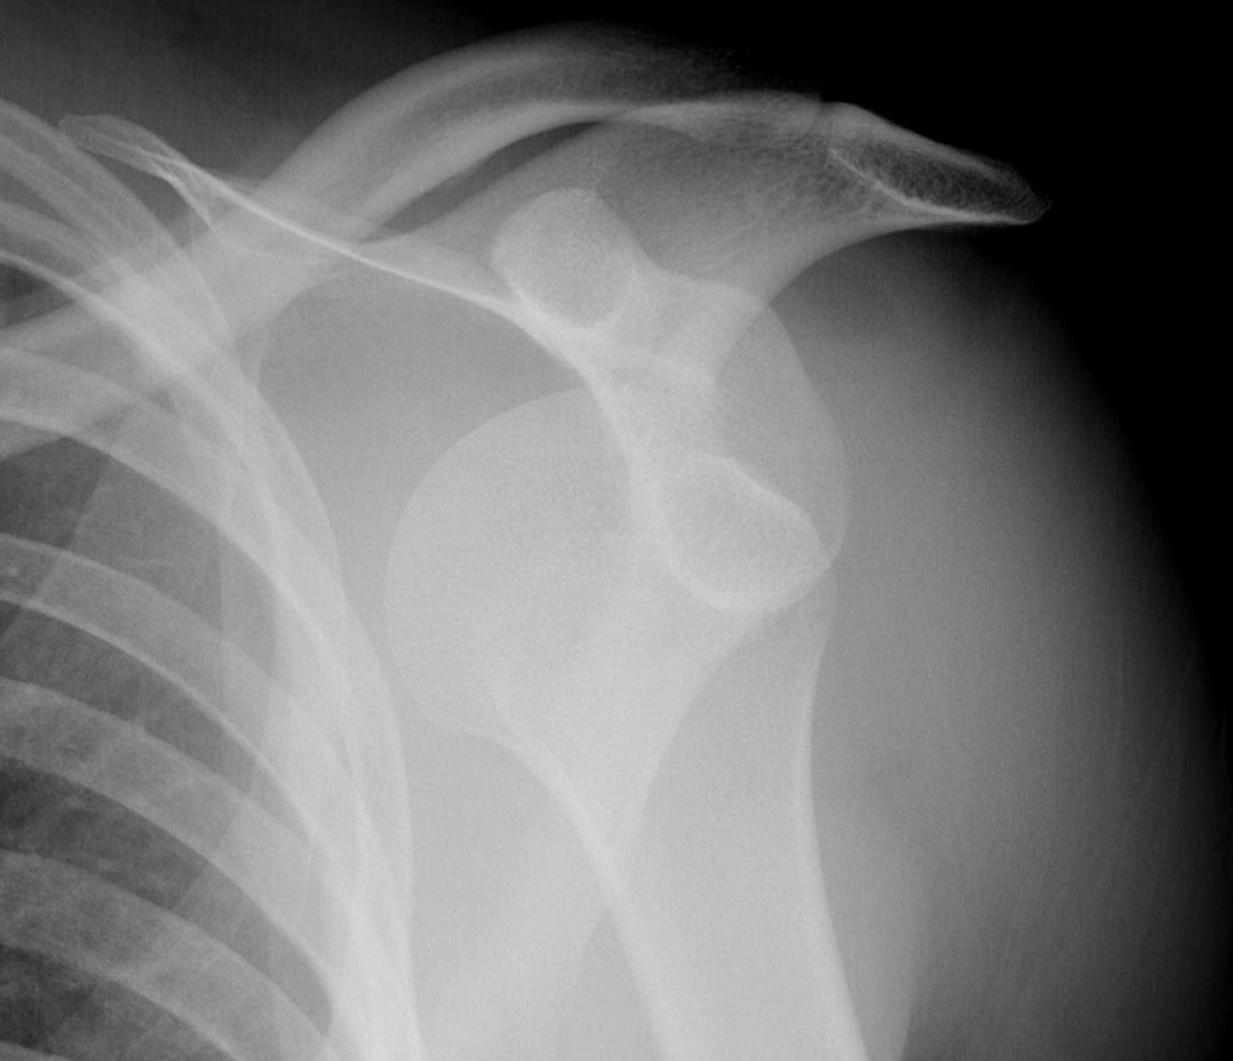

Xray

True AP

Scapular Lateral

Axillary Lateral

Garth (aim beam caudally)

Bony bankart / glenoid rim fractures

Acute bony bankart / glenoid rim fractures